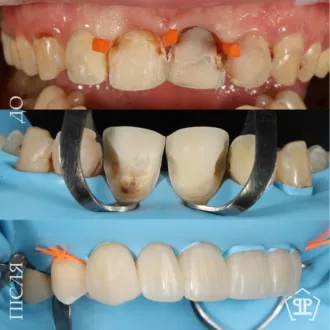

Замена старых композитных реставраций со вторичным кариесом